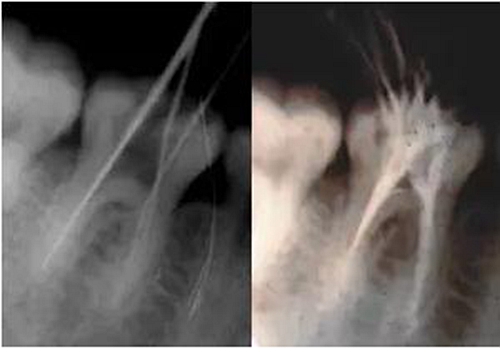

最后來玩一個根管治療質(zhì)量的評估——下圖是武大彭彬教授的一個病例,仔細(xì)觀察可以挑出一點問題,但問題事出有因!看看你的“眼力”如何——問題在那里?教授的專業(yè)水平是不用懷疑的,那么事出的原因可能是什么?

問題答案:這個病例的問題主要反應(yīng)在開髓的洞形修整,注意觀察該牙X-RAY的左側(cè)洞壁,如果常規(guī)情況制備成這樣是由于裂鉆破壞了洞壁和洞底所形成的臺階。如果評估根管治療的質(zhì)量那是要扣分的!但這個病例仔細(xì)觀察洞壁形態(tài)就可以看出:該病例屬于再治療的病例,因此還是屬于一個理想的病例。